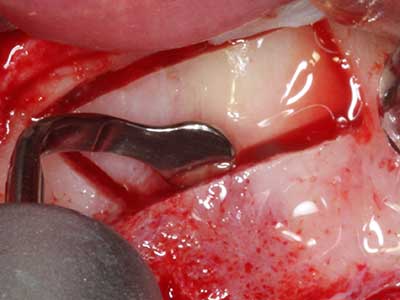

Indicazione: prelievo osseo autologo

I trapianti autologhi dell'osso si eseguono in forma di blocchi, strati e anelli, anche in combinazione con materiali di riempimento tipo microframmenti. Se il sito dell'impianto viene preparato contemporaneamente all'accrescimento, diversi sistemi di filtraggio dell'osso si sono rivelati efficaci per la raccolta dei microframmenti ossei risultanti. Come metodo alternativo, il sito dell'impianto può essere preparato utilizzando un dispositivo a bassa velocità senza irrigazione. Senza l'inserimento di un impianto, è possibile raccogliere i microframmenti ossei dalla periferia mediante bisturi affilati per tessuto osseo. Ciò può essere eseguito anche con la piezochirurgia mediante appositi raccordi che raccolgono microframmenti ossei di qualità più elevata rispetto a quelli raccolti con trapani rotondi, come è stato confermato in uno studio comparativo dei due metodi (Chiriac, Herten et al. 2005).

La piezochirurgia presenta altri vantaggi per quanto riguarda la raccolta di blocchi ossei. Oltre all'elevata precisione dell'osteotomia appena descritta, l'utilizzo di puntine per sega molto sottili permette di minimizzare in maniera significativa la perdita di materiale. È molto probabile che si verifichi una maggiore perdita di materiale durante la raccolta utilizzando puntine di strumenti più spessi, in particolare delle frese Lindemann (Lakshmiganthan, Gokulanathan et al. 2012). La separazione basale, necessaria in particolare per i trapianti di blocchi nella zona retromolare, viene semplificata grazie a seghe specificatamente progettate di forma rettangolare; di conseguenza la piezochirurgia è considerata una procedura precisa, semplice e sicura per la raccolta di blocchi di osso nella zona retromolare (Happe 2007) (figg. 1-12).